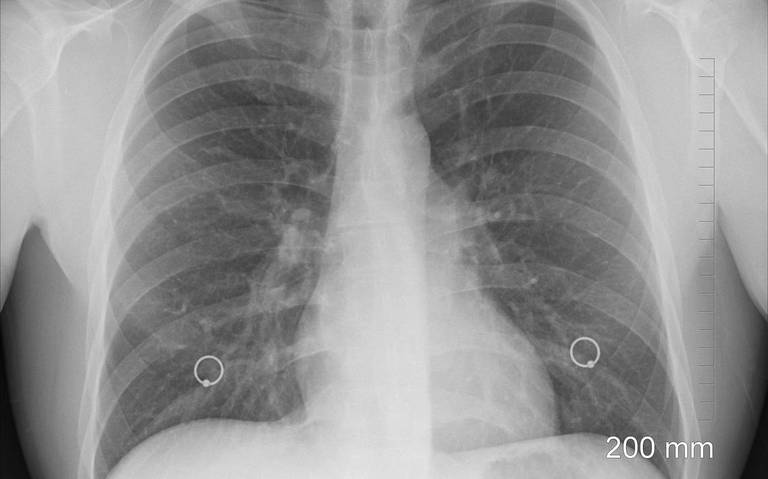

Suben los casos de tuberculosis en Tabasco

Tabasco.- En lo que va del año, se han estudiado 500 casos de Tuberculosis en Tabasco, reportó la Jurisdicción Sanitaria del municipio de Centro, por ello, ha incrementado en un 68 por ciento la búsqueda de personas que han estado en contacto con los pacientes con la enfermedad.

El jefe de la jurisdicción, Carlos de la Cruz Alcudia, expuso que diez de cada 100 casos han salido positivos, sin embargo, esto ha ido al alza porque, al momento de obtener los resultados de un paciente sospechoso, éste ya hizo contacto con más personas dispersando el virus.